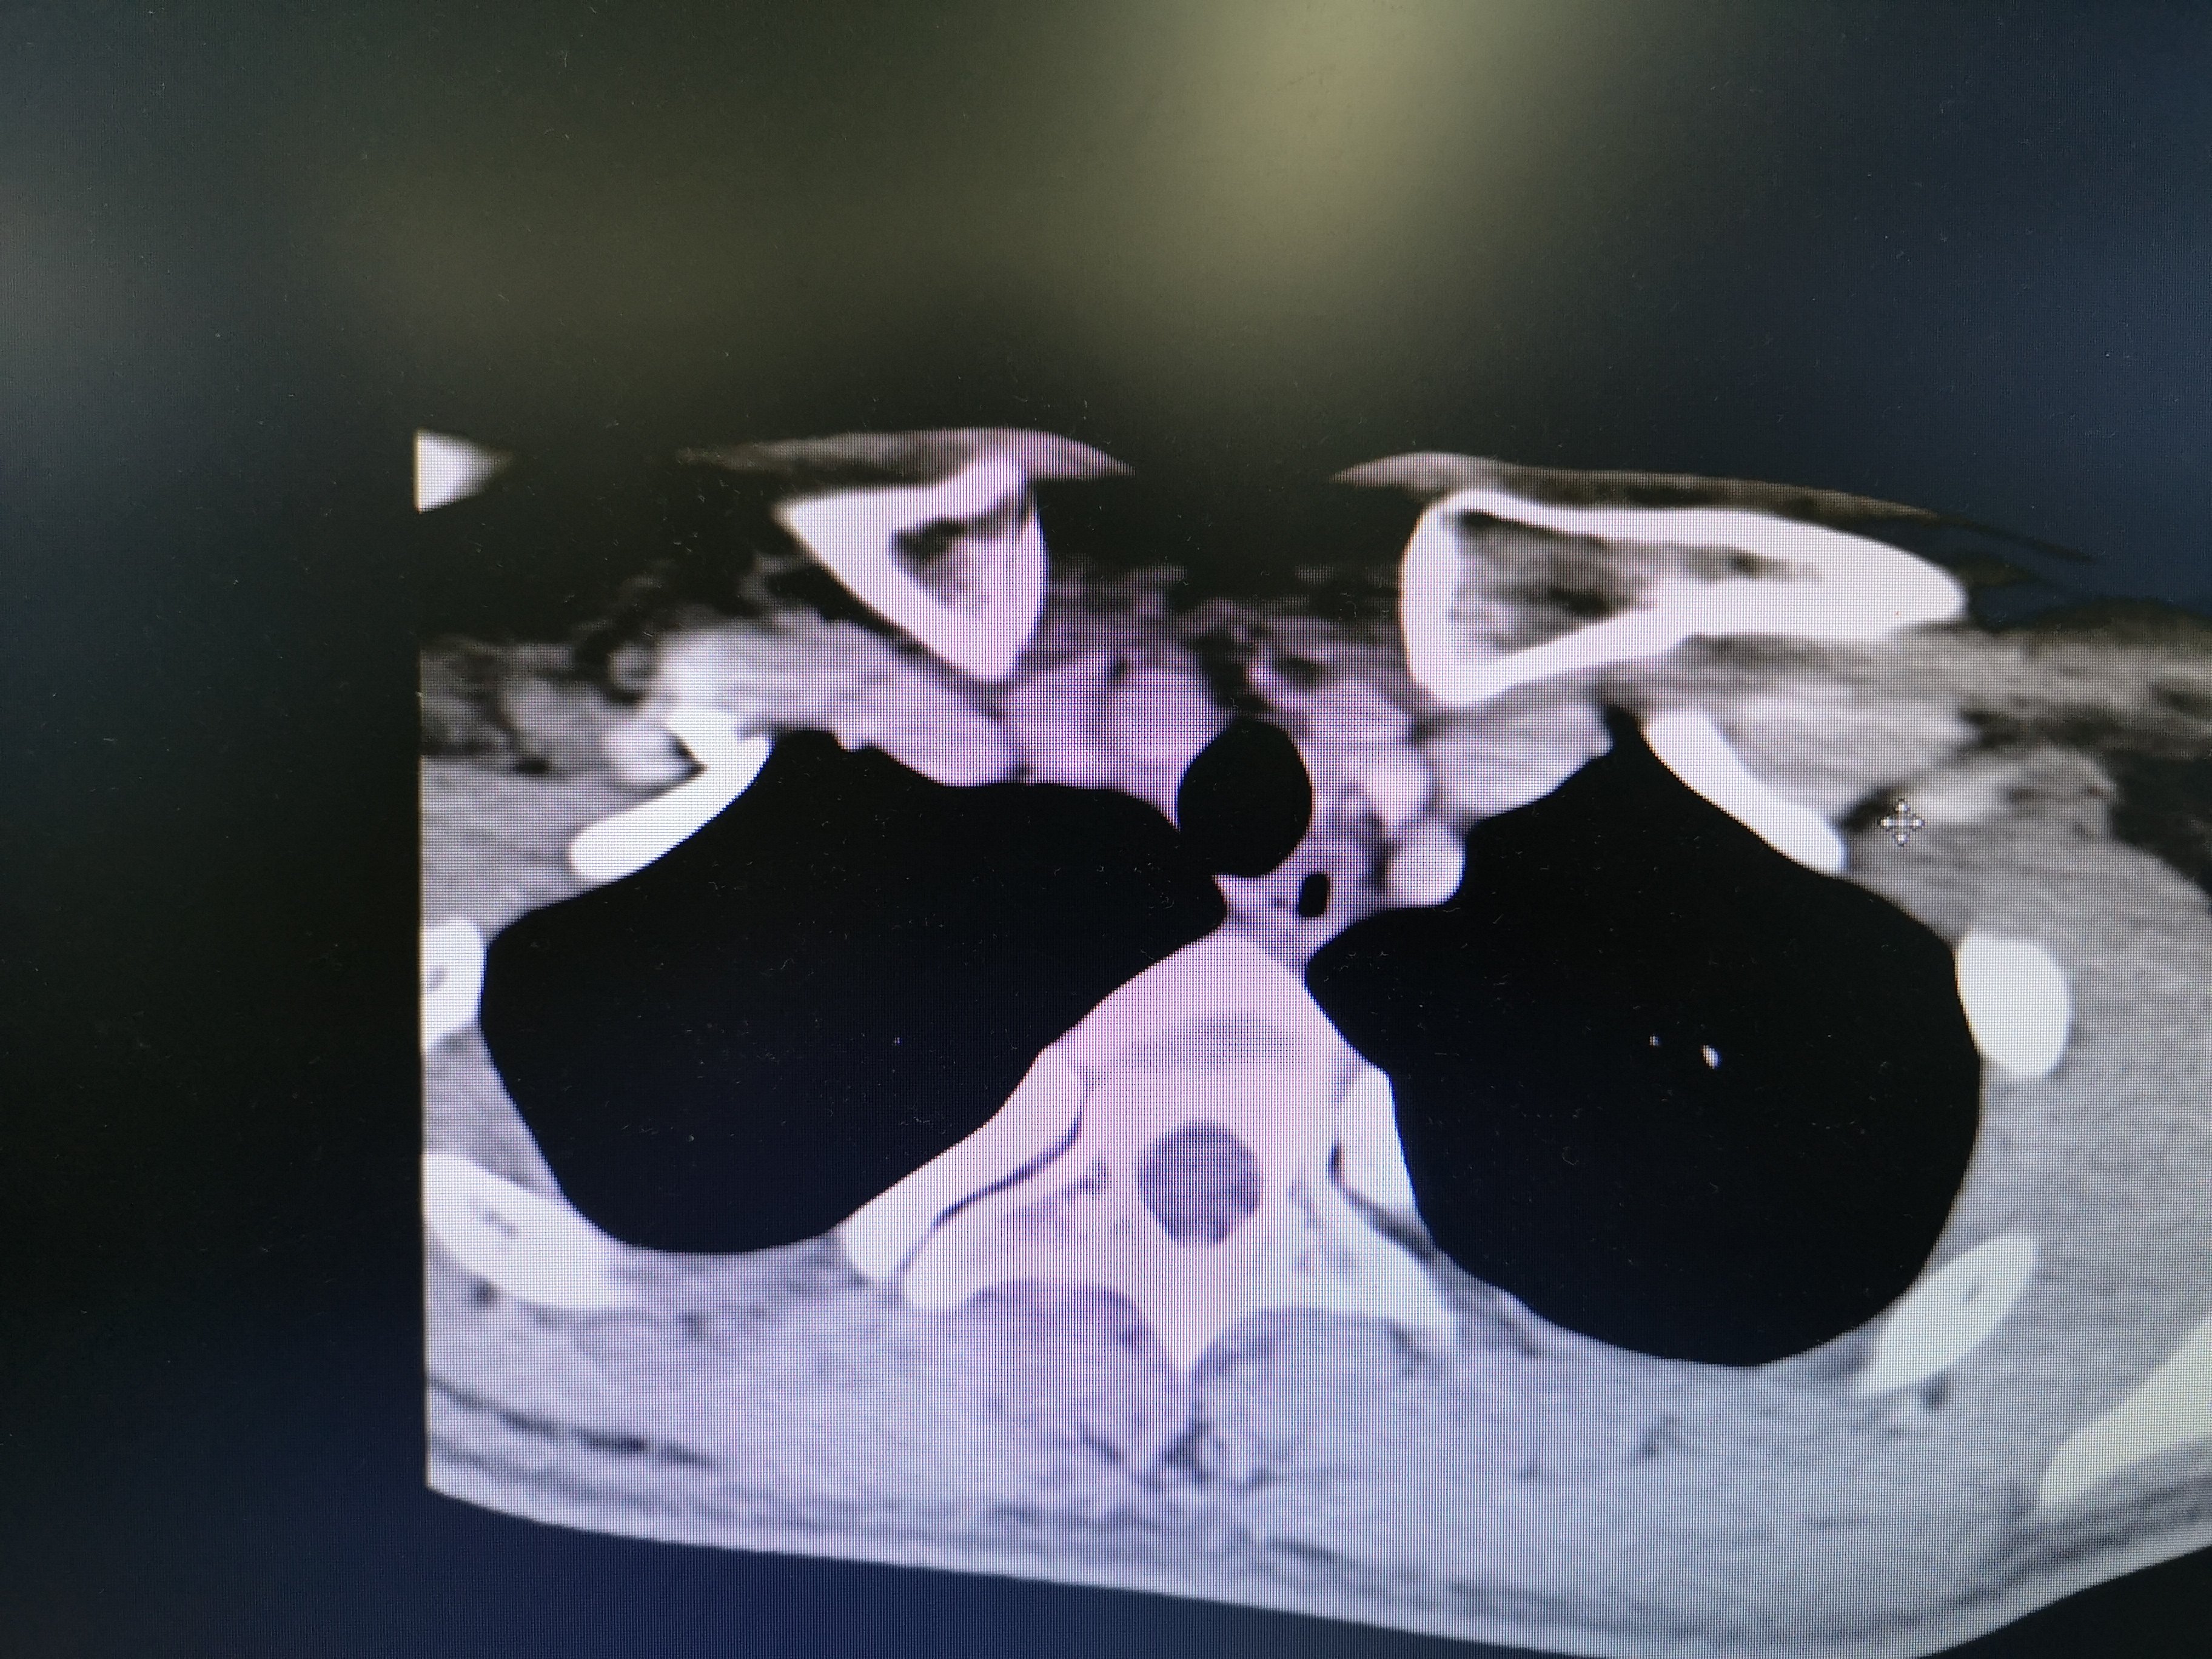

病例2 右2,右4R区,左6区残留,颈部切口清扫,未开胸